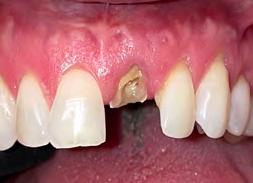

3. Image 3a: Tooth #9 was extracted with minimal flap elevation, preserving the papillae. Image 3b: A 3.6 x 15 mm implant was placed in a fully guided manner with a palatal bias to maximize the facial gap dimension, achieving a +2mm gap.

4. Image 4a: The underside of the periosteum was incised just apical to the mucogingival junction, and a supra-periosteal pocket was created using sharp dissection with a #15 blade. Image 4b: The facial gap was packed with 50 mg of Geistlich Bio-Oss Collagen®. A cover screw was temporarily placed to prevent bone graft granules from entering the implant chamber.

3. Minimally invasive removal of #12 using only a buccal approach mini-flap showing an intact buccal plate with immediate placement of the implant (1 mm below the intact buccal wall) in a screw-retained position. A 3mm buccal gap is measured and a 1.5mm palatal gap.

4. Both the buccal and palatal gaps have been packed with Geistlich Bio-Oss Collagen® hydrated with Gem 21S. I prefer to squeeze Geistlich Fibro-Gide® between thumb and forefinger, prior to placement. A dry-carved piece of Geistlich FibroGide® is in position thinned approximately 2mm with beveling laterally and coronally with a new #15 blade.